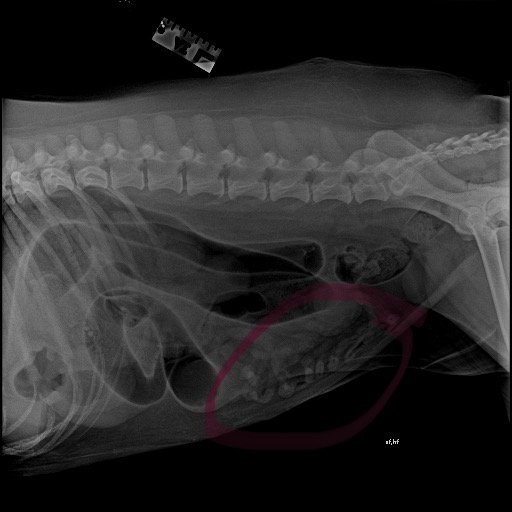

Hi friends! Our beloved family dog, Teddy, needs to undergo emergency surgery this week, which we cannot afford. He ingested what looks to be a necklace and it has caused an internal blockage, which we noticed as he has almost completely stopped eating for the past 2 weeks. We so badly want to see our sweet boy well and eating again :( The quote from different vets we reached out to were around $4000-$6000